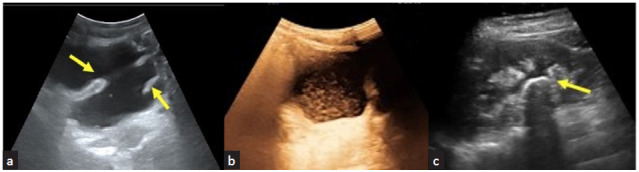

Point of care ultrasound (POCUS) is gaining wide recognition in its bedside applications. The day-to-day practice of nephrology requires several ultrasonographic parameters for diagnosis. Hence, familiarity with basics of renal ultrasound imaging is becoming a necessary skill for every nephrologist. This review provides an overview of the normal and abnormal findings in a graft kidney and its environment throughout graft survival and after its failure. The correlative understanding of the clinical features with image findings provides the greatest advantage in applying POCUS at the bedside.

Abstract Image